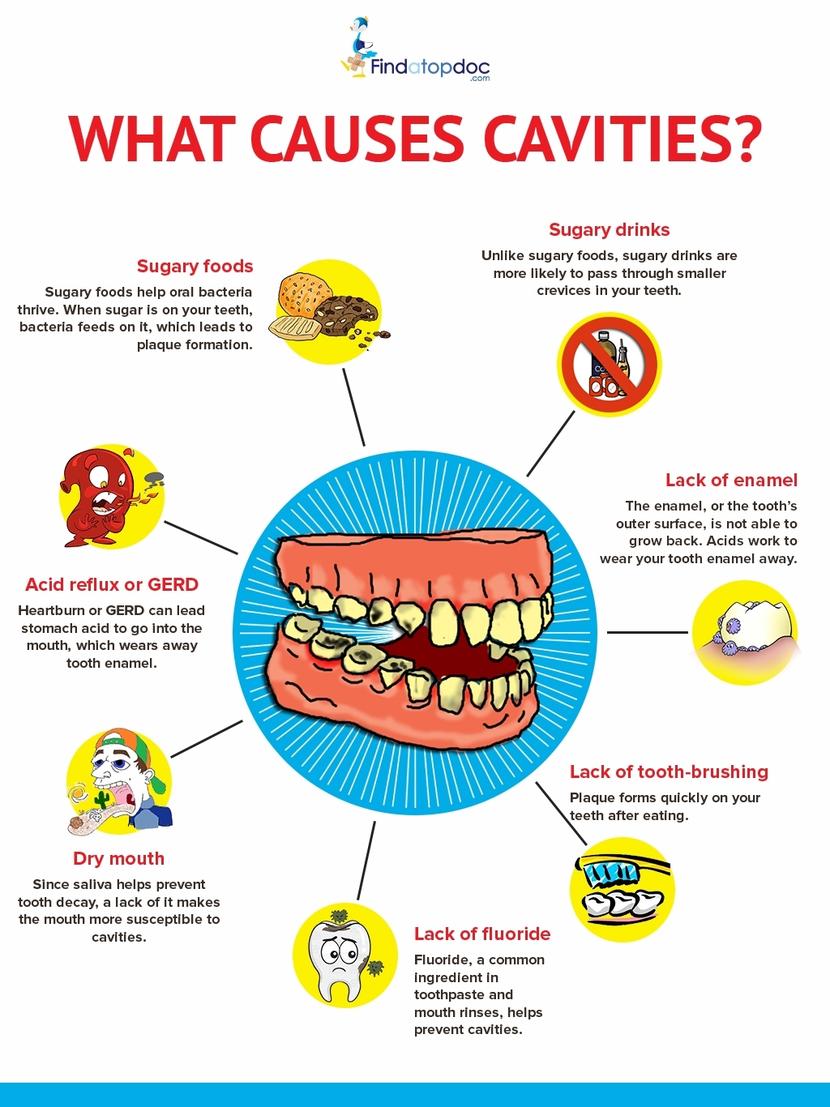

Cavities/ Tooth Decay: Symptoms, Causes, Treatment, And Diagnosis

www.findatopdoc.com

www.findatopdoc.com

causes cavities tooth decay prevent cause symptoms may food main findatopdoc wine process important facts treatment